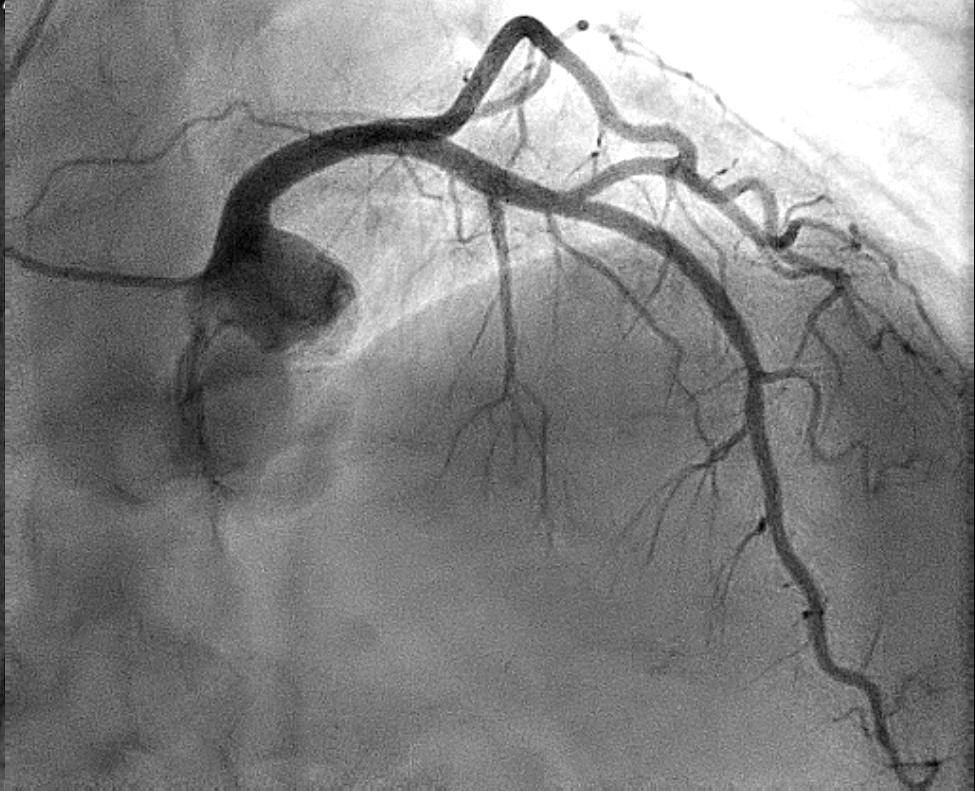

Det er vanlig at ANOCA-pasienter har ikke-signifikante aterosklerotiske plakk i epikardielle arterier ved CT

Tabell 1. Mekanismer ved myokardiskemi.

koronarkar eller koronar angiografi (Figur 1). Dersom man er usikker på om disse forandringene har betydning for koronar blodstrøm, bør det gjøres intrakoronar trykkmåling. Det er heller ikke uvanlig at pasienter som tidligere er revaskularisert har vedvarende symptomer der fornyet utredning viser åpne stenter eller bypassgraft. I slike tilfeller må man mistenke CMD som årsak til symptomene. ANOCA oppstår således over hele spekteret av aterosklerotisk sykdom. Spasmeangina som forårsakes av makrovaskulær spasme i epikardielle arterier inkluderes også i ANOCA-gruppen. Dette er en pasientgruppe som kan være vanskelig å diagnostisere der anamnesen som regel skiller seg fra andre pasienter med kronisk koronarsyndrom (5). Spasmeangina omtales derfor i et eget punkt senere.